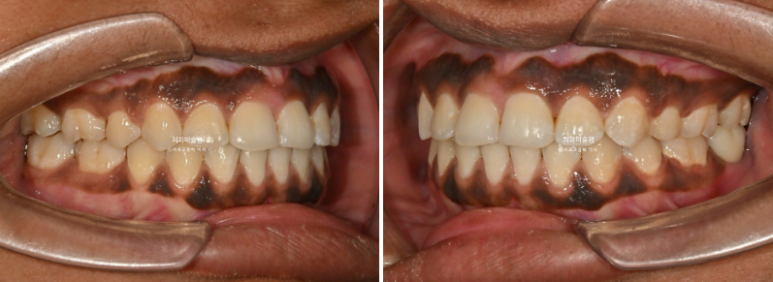

The patient’s broad smile, showing even the second molars, is particularly attractive. This type of “big smile” is relatively uncommon among Asian patients.

23.07~25.12

With the protruded anterior teeth corrected, the smile appears much more refined and harmonious.

The lip protrusion has also been resolved.